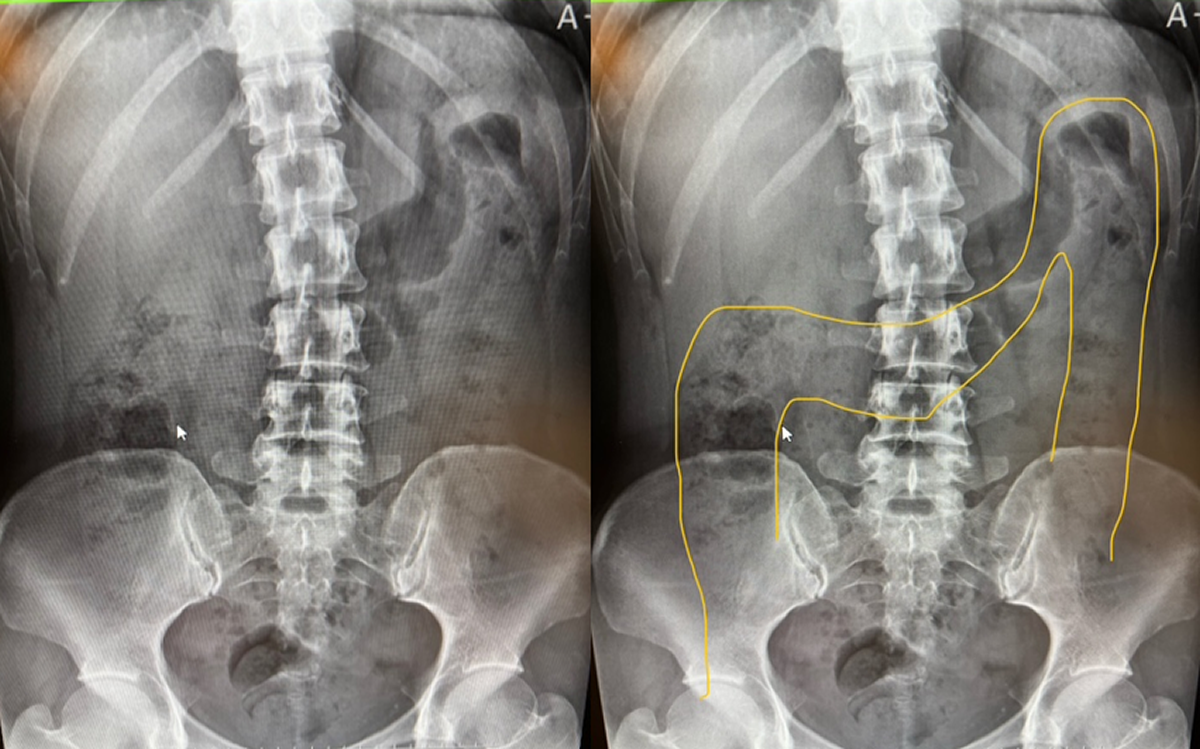

≪落下腸・臥位(横になって撮影)≫

横行結腸が上に上がり、本来の位置に近づいている